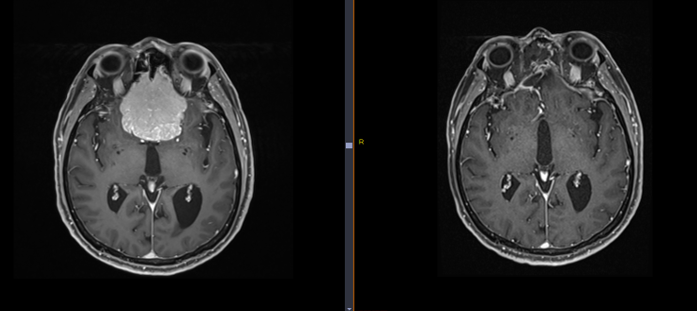

Méningiome ethmoïdal avant et après chirurgie